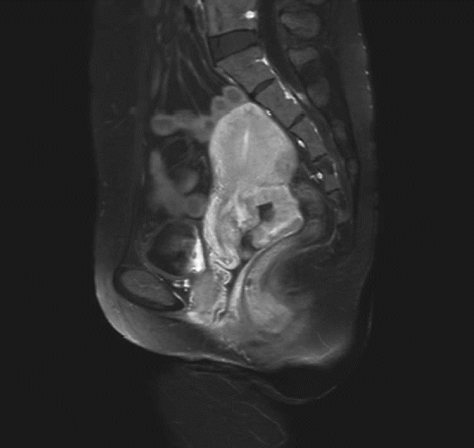

ⅠB1期宫颈癌MR ⅠB2期宫颈癌MR

ⅡA1期宫颈癌MR ⅡA2期宫颈癌MR

ⅡB期宫颈癌MR ⅢA期宫颈癌MR

ⅢB期宫颈癌MR ⅣB期宫颈癌MR